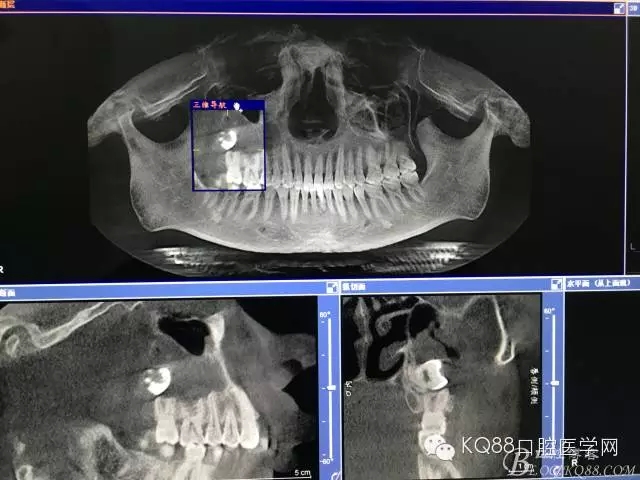

圖3.加拍CBCT影像檢查:18位于上頜竇內(nèi),并導(dǎo)致右側(cè)上頜竇粘膜炎性增生。18牙冠的合面朝向頰側(cè)。并且與17頰根緊密相鄰。